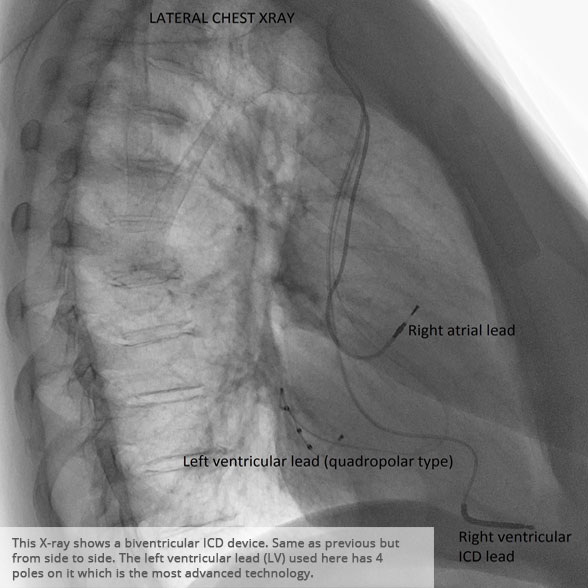

Lateral chest x-ray 2 Lateral chest x-ray 2

BI-VENTRICULAR PACEMAKERS

Bi-ventricular pacemakers are used for the treatment of suitable patients with heart failure who are already on medication but who suffer from a lack of synchrony between the right and left ventricular contraction. This is most commonly caused by an electrical delay (left bundle branch block LBBB) in transmission of signals to the main pumping chamber (called the left ventricle) and is relatively common in patients with advanced heart failure. This delay process commonly worsens the symptoms of heart failure and it is not generally influenced by medication alone.

Although not all patients universally respond to bi-ventricular pacing (or cardiac resynchronisation therapy/CRT), patients with more advanced dys-synchrony tend to experience remarkable improvement. Bi-ventricular ICDs have the additional benefit of recognising life threatening arrhythmia and deliver both fast pacing bursts or shocks to restore normal heart rhythm.